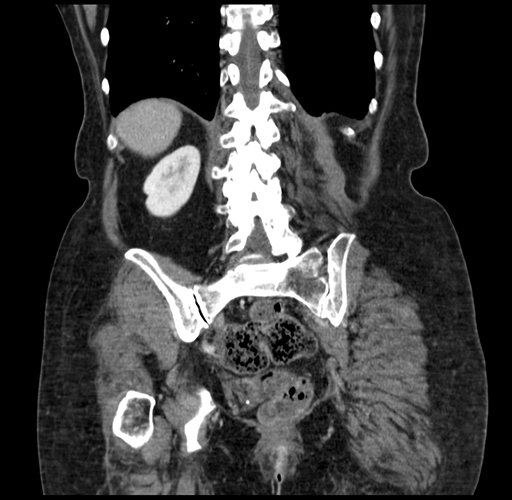

Pre-Chemo: Coronal Venous

Coronal Venous